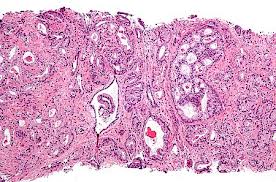

По мнению руководителя группы исследователей, профессора Пэтти Эндрю, необходимо учитывать, что рак принимает новые формы, часто протекает бессимптомно до запущенных стадий. По ее мнению, задача ранней диагностики состоит в том, чтобы определить начало развития рака за шесть и более месяцев до появления первых клинических симптомов болезни. Если установлен рак предстательной железы на ранней стадии, у специалистов появляется выбор, как лечить, применить ли гормональную терапию, радиационную или хирургическое пособие, а также возможность использовать наиболее щадящую технику, уменьшить влияние последствий операции на образ жизни пациента.

При этом исследователи отмечают, что при условии отсутствия генетической предрасположенности к заболеваемости раком предстательной железы необходимо начать проверяться с 35-летнего возраста, так как после этого возраста риск заболевания достигает одного к шести. Специалисты предлагают девять факторов образа жизни, через которые можно уменьшить риск фактического развития опухоли до 50 %: